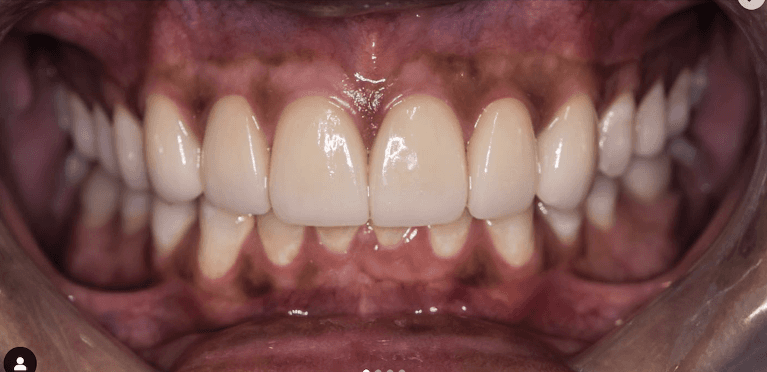

Upper & Lower, All on 4 fixed implant teeth with finals. Patient went home with temp fixed teeth the same day.